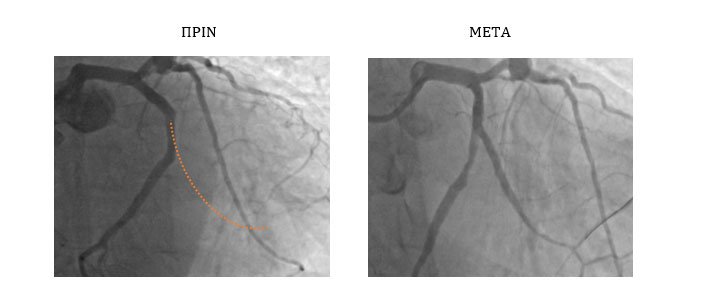

Ασθενής 70 ετών για αγγειοπλαστική χρόνιας ολικής απόφραξης ενός μεγάλου μεγέθους επιχειλίου κλάδου, λόγω συμπτωμάτων στηθάγχης, μετά από αποτυχημένες προσπάθειες διάνοιξής του. Στην κατηγοριοποίηση του βαθμού δυσκολίας, η συγκεκριμένη βλάβη κατατάσσεται στην κατηγορία των πλέον δύσκολων CTO (J-CTO score 3). Η επέμβαση πραγματοποιήθηκε επιτυχώς από την κερκιδική αρτηρία.